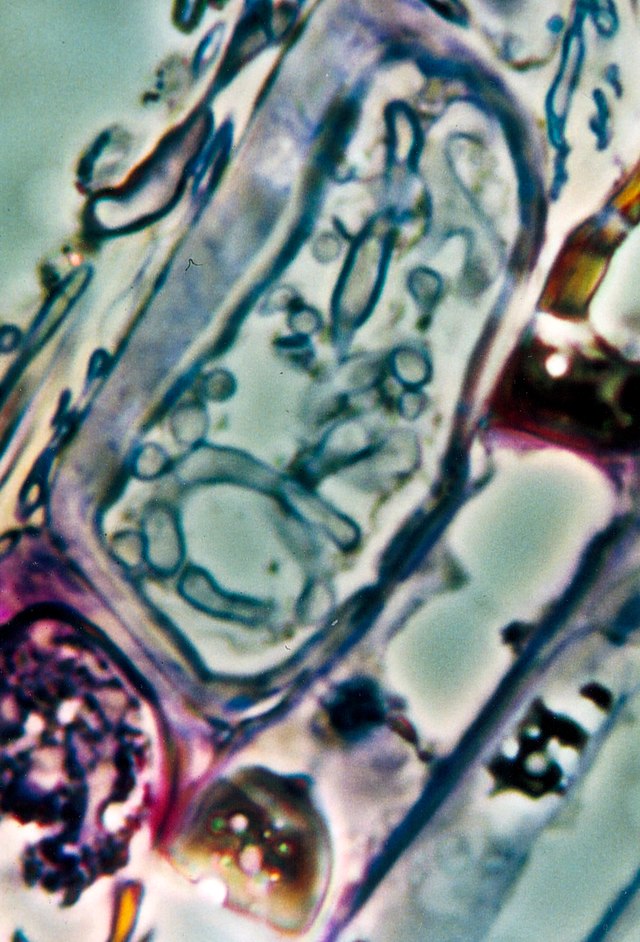

Raziskovalke in raziskovalci so dodatno preverjali prisotnost gliv v tkivnih preparatih raka trebušne slinavke, dojk, pljuč in jajčnikov ter kožnega raka s štirimi različnimi metodami barvanja. Glive, ki so jih videli na tkivnih preparatih, so večinoma rasle v rakavih ali imunskih celicah.

Vir slike: https://commons.wikimedia.org/